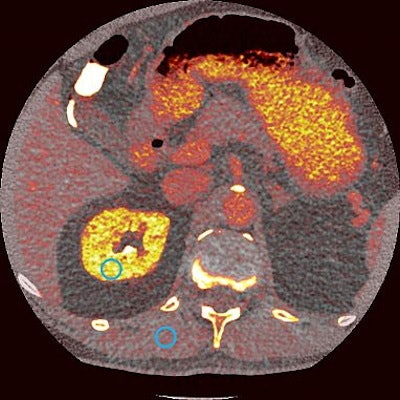

On the same day, the FDA also approved Novartis' kit (Locametz) for the preparation of the radiotracer gallium-68 (Ga-68) PSMA-11, which is used in PET imaging to identify metastatic prostate cancer tumors.

The approvals mark significant milestones in the emerging field of theranostics -- a term derived from "therapeutics" and "diagnostics" to describe the use of targeted radiopharmaceuticals to both image and treat cancer.

The FDA granted priority review for Lu-177 PSMA-617 in September 2021 based on positive data from the multicenter phase III VISION study. In 800 men with PSMA-positive prostate cancer that had progressed despite standard treatments, 38% showed a reduced risk of death and a 60% reduced risk of progression when treated with Lu-177 PSMA-617.